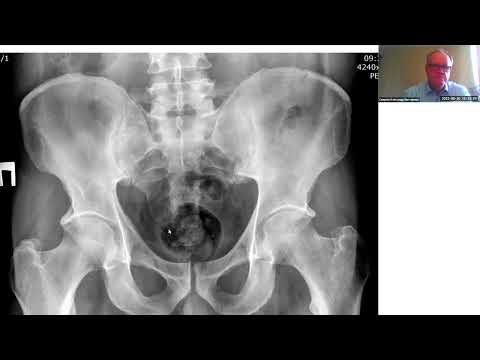

Диагностика и комплексное лечение туберкулеза крупных суставов

Особенности диагностики и лечения туберкулеза у детей и подростков